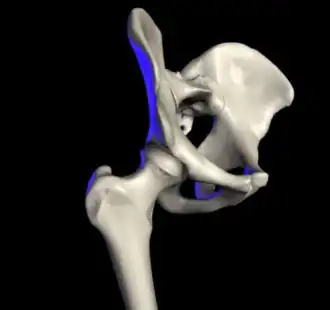

![]() Right hip of a female human | |

Articulation

The hip joint or coxofemoral joint[5][6] is a ball and socket synovial joint formed by the articulation of the rounded head of the femur and the cup-like acetabulum of the pelvis.[7] The socket of the acetabulum is pointing downwards and anterolaterally. The socket is also turned such that the outer edge of its roof is more lateral than outer edge of the floor.[7] It forms the primary connection between the bones of the lower limb and the axial skeleton of the trunk and pelvis. Both joint surfaces are covered with a strong but lubricated layer called articular hyaline cartilage.

The cuplike acetabulum forms at the union of three pelvic bones — the ilium, pubis, and ischium.[8] The Y-shaped growth plate that separates them, the triradiate cartilage, is fused definitively at ages 14–16.[9] It is a special type of spheroidal or ball and socket joint where the roughly spherical femoral head is largely contained within the acetabulum and has an average radius of curvature of 2.5 cm.[10] The acetabulum grasps almost half the femoral ball, a grip deepened by a ring-shaped fibrocartilaginous lip, the acetabular labrum, which extends the joint beyond the equator.[8] The centre of the acetabulum (fovea) does not articulate to anything. Instead, it is lined with fat pad and attached to ligamentum teres. The acetabular labrum is horse-shoe shaped. Its inferior notch is bridged by transverse acetabular ligament.[7] The joint space between the femoral head and the superior acetabulum is normally between 2 and 7 mm.[11]

Capsule

Proximally, capsule of the hip joint is attached to the edge of the acetabulum, acetabular labrum, and transverse acetabular ligament. Distally, it is attached to the trochanters of the femur and intertrochanteric line anteriorly. Posteriorly, it is attached to a junction between medial two-thirds and lateral one-third of the femoral neck,[7] one finger breadth away from the intertrochanteric crest.[24] From its attachment at the femoral neck, the fibres of the capsule reflected backwards towards the acetabulum, carrying retinacula vessels supplying the femoral head.[7] The part of femoral neck outside the capsule is shorter in front than posteriorly.[24]

Ligaments

The hip joint is reinforced by four ligaments, of which three are extracapsular and one intracapsular.

The extracapsular ligaments are the iliofemoral, ischiofemoral, and pubofemoral ligaments attached to the bones of the pelvis (the ilium, ischium, and pubis respectively). All three strengthen the capsule and prevent an excessive range of movement in the joint. Of these, the Y-shaped and twisted iliofemoral ligament is the strongest ligament in the human body. It has a tensile strength of 350 kg.[24] Iliofemoral ligament is a thickening of the anterior capsule extending from anterior inferior iliac spine to intertrochanteric line.[7] Ischiofemoral ligament is the thickening of posterior capsule of the hip and pubofemoral ligament is the thickening of the inferior capsule.[7] In the upright position, iliofemoral ligament prevents the trunk from falling backward without the need for muscular activity, thus preventing excessive hyperextension. In the sitting position, it becomes relaxed, thus permitting the pelvis to tilt backward into its sitting position. Ischiofemoral prevents excessive extension and the pubofemoral ligament prevents excess abduction and extension.[26]